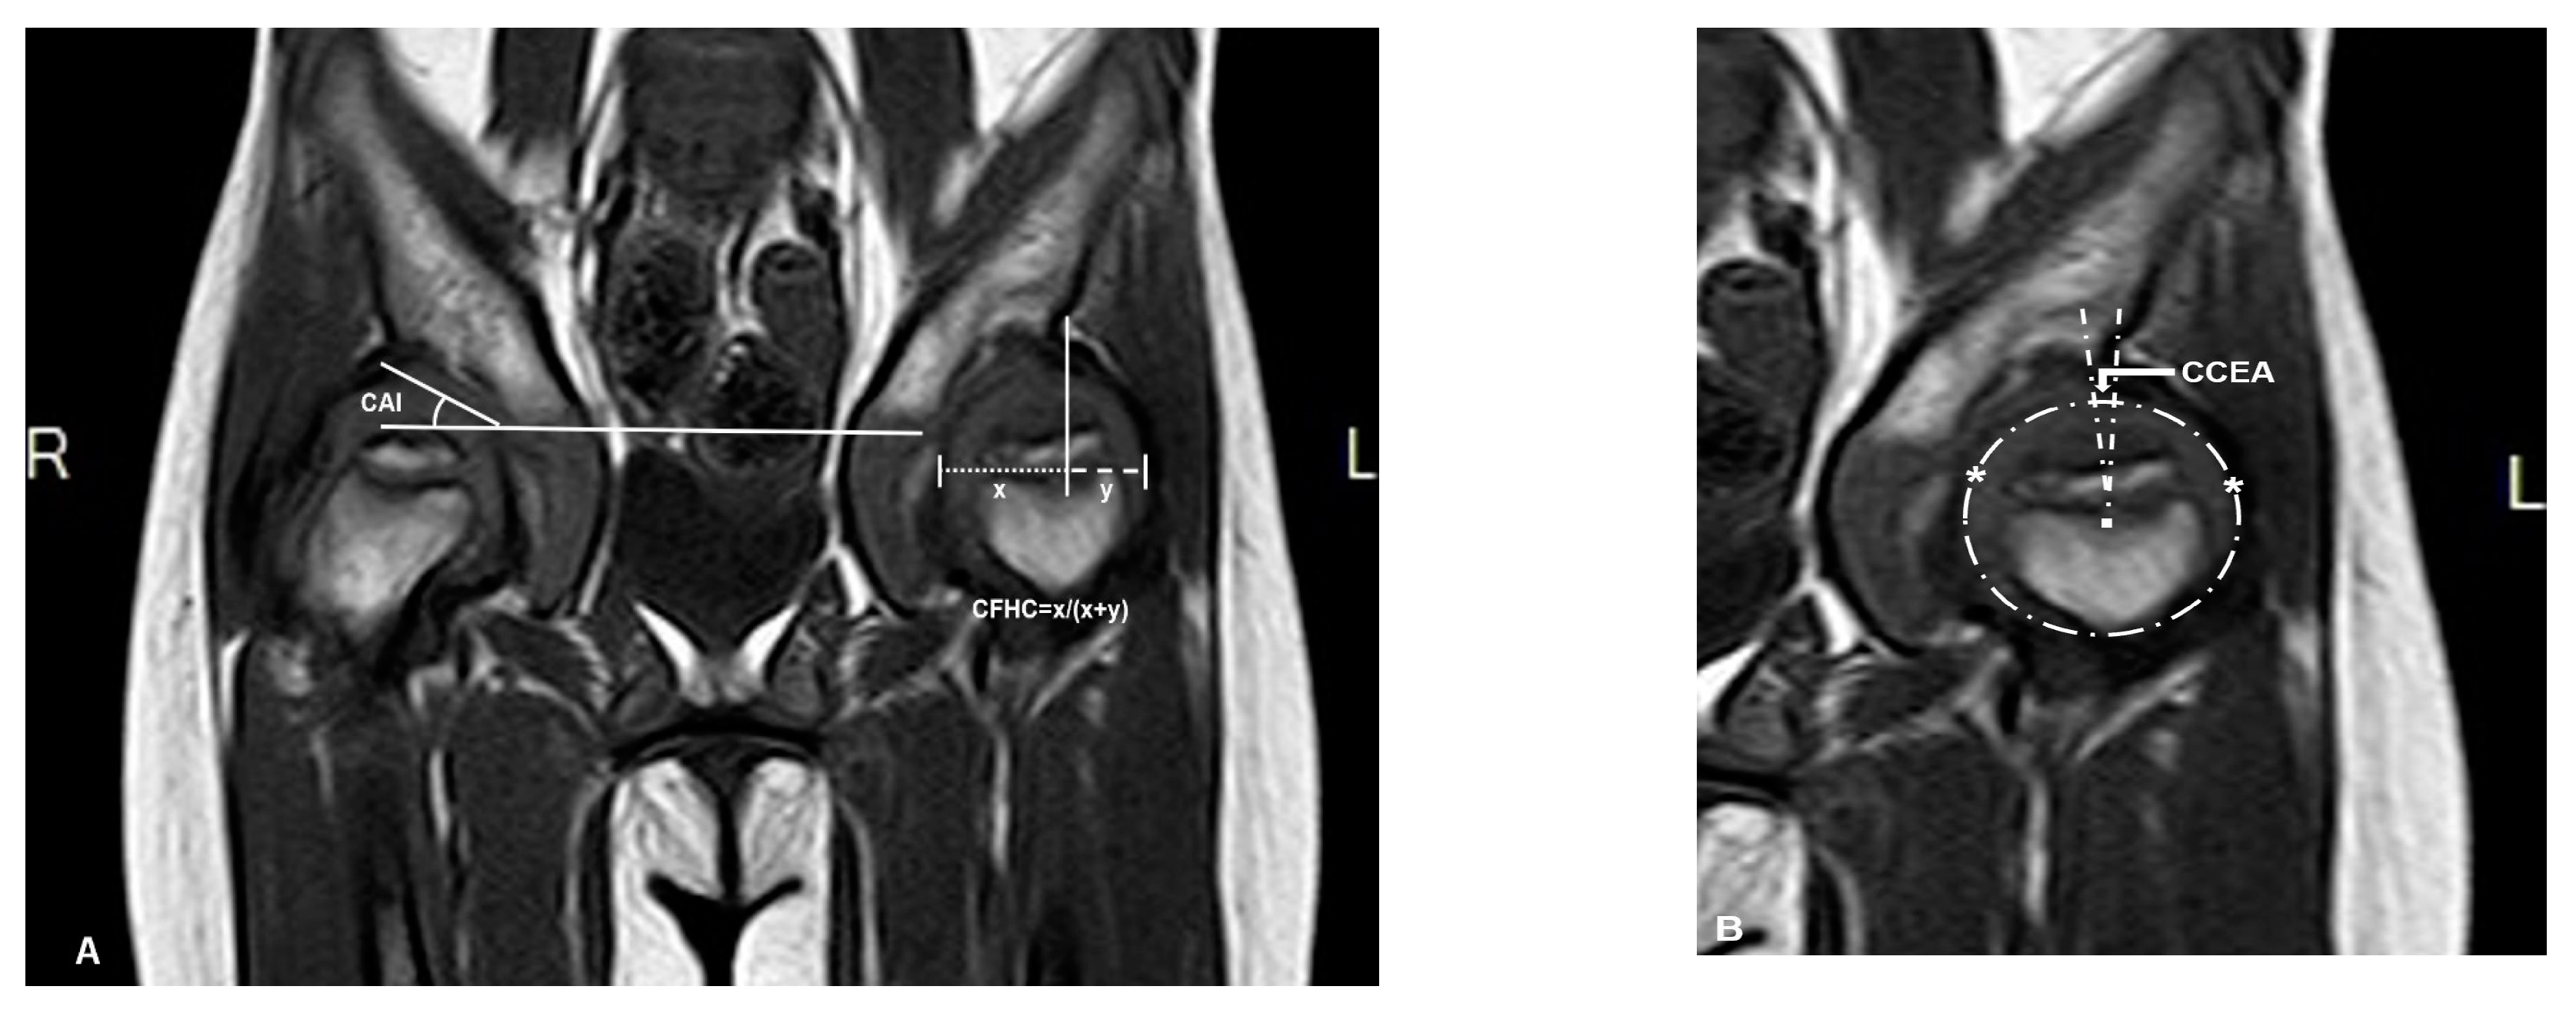

2.1. Radiographic Measurements and Analysis

| Range of Age(y) | Numbers of Patients | AI (°) | CAI (°) | CEA (°) | FHC (%) | NSA (°) | |||||

|---|---|---|---|---|---|---|---|---|---|---|---|

| MPS-IVA | NC † | MPS-IVA | NC† | MPS-IVA | NC ‡ | MPS-IVA | NC ‡ | MPS-IVA | NC § | ||

| 3 to 4 | 3 | 33 ± 2 | 19.89 | 19 ± 5 | 8.17 | −18 ± 10 | 23 | 29 ± 8 | 83–84 | 145 ± 8 | 145 |

| 4 to 5 | 6 | 33 ± 5 | 18.22 | 22 ± 6 | 7.9 | −26 ± 10 | 23 | 27 ± 18 | 79–84 | 143 ± 8 | 145 |

| 5 to 6 | 1 | 36 ± 1 | 18.51 | 24 ± 2 | 8.4 | −21 ± 4 | 23 | 30 ± 12 | 79–82 | 143 ± 4 | 142 |

| 6 to 7 | 2 | 35 ± 4 | 17.91 | 23 ± 1 | 8.19 | −9 ± 1 | 24 | 45 ± 8 | 80–82 | 147 ± 6 | 142 |

| 7 to 8 | 1 | 39 ± 1 | 18.25 | 25 ± 2 | 8.05 | −33 ± 1 | 26 | 9 ± 2 | 80–82 | 149 ± 5 | 142 |

| 8 to 9 | 4 | 40 ± 2 | 17.64 | 24 ± 4 | 8.15 | −16 ± 14 | 25 | 25 ± 9 | 81–82 | 150 ± 4 | 142 |

| 9 to 10 | 2 | 39 ± 6 | 16.40 | 23 ± 5 | 7.87 | −29 ± 5 | 25 | 18 ± 4 | 81 | 148 ± 4 | 138 |